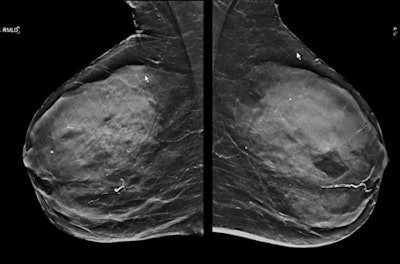

Dense breasts

Another hot topic at the EUSOBI meeting promises to be the role of MRI in screening women with dense breasts, following the start of the ECOG/ACRIN (Eastern Cooperative Oncology Group and the American College of Radiology Imaging Network) abbreviated breast MRI screening trial (EA1141) activated earlier this month.

Kuhl, who is the co-principal investigator of this trial, hopes it will change the landscape of breast cancer screening and increase women's access to breast MRI. To date, the only tried and proven screening method for decreasing mortality from breast cancer is mammography, but mammography can miss biologically aggressive cancers, especially in women with dense breast tissue, while picking up indolent slow-growing disease, she explained.

"Mammography detects many breast cancers by depicting regressive changes such as calcifications and architectural distortions, namely hallmarks of pathophysiological changes that reflect slowed growth and cell death. This leads to an effect known as the 'length-time bias.' Overdiagnosis is nothing but an extreme form of length-time bias," Kuhl said.

Conversely, breast MRI is associated with what could be called a 'reverse-length-time bias,' and it works by depicting angiogenic and protease activity, the pathophysiological processes of DCIS and cancers that are closely associated with carcinogenesis and metastatic progression, she explained. "The more aggressive a cancer is, the better seen it is on MRI," she noted.

Overdiagnosis is only one side of the problem, according to Kuhl. The other is underdiagnosis: the failure to pick up cancers that require treatment. Despite decades of mammographic screening, breast cancer continues to represent a major cause of cancer in women, suggesting a need for improved screening strategies.

"Screening is not about finding all cancers and their precursors as soon as possible. Rather, the goal is to find early those cancers that have the potential to kill. Screening tests need to have a sensitivity profile that highlights rapidly growing cancer while downplaying biologically unimportant disease such as low-grade DCIS. And that's exactly what MRI offers," she said.